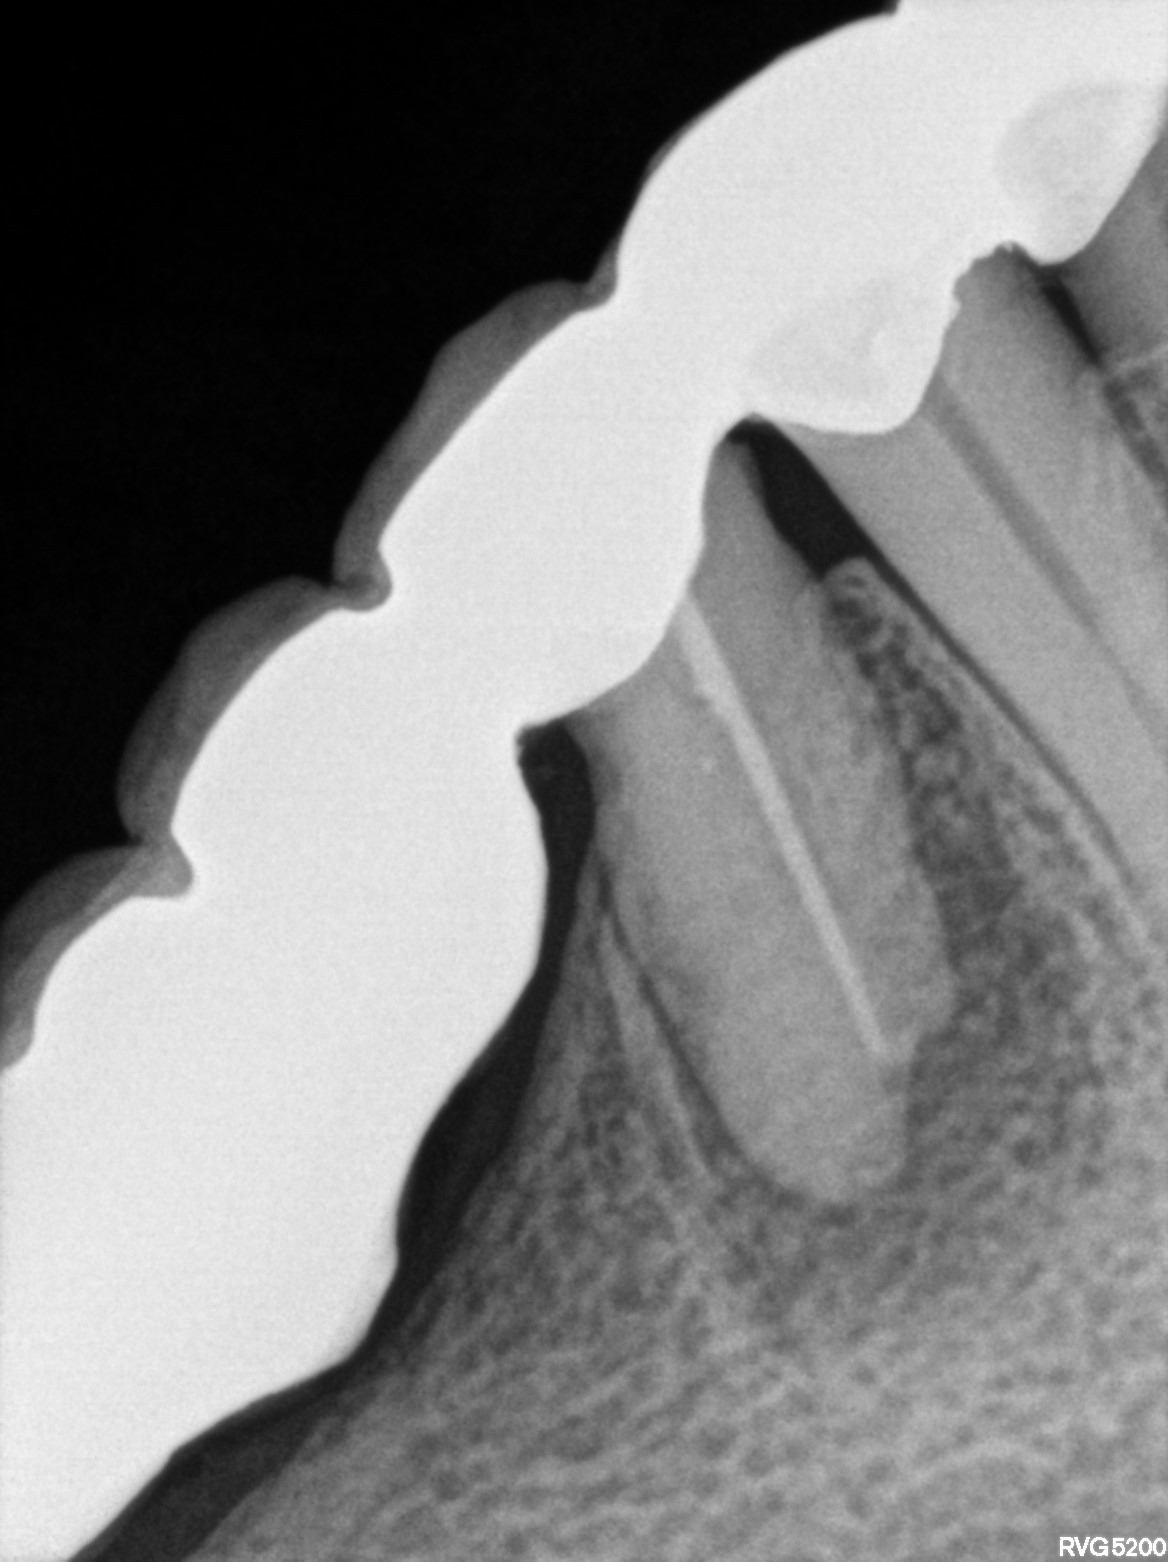

Dental Radiographs FHIR: DocumentReference · LOINC 24641-7

xray_1764234367_1.jpg

24641-7